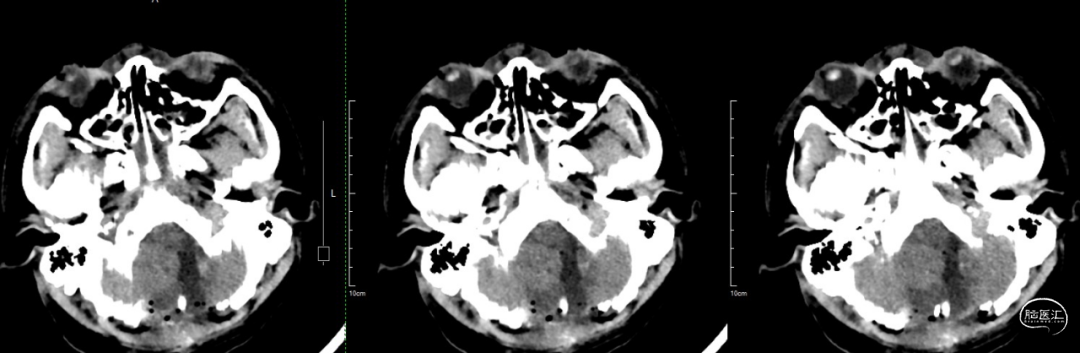

术后当天CT:肿瘤全切,术区无出血,幕上脑室积血,考虑术中出血倒灌所致。